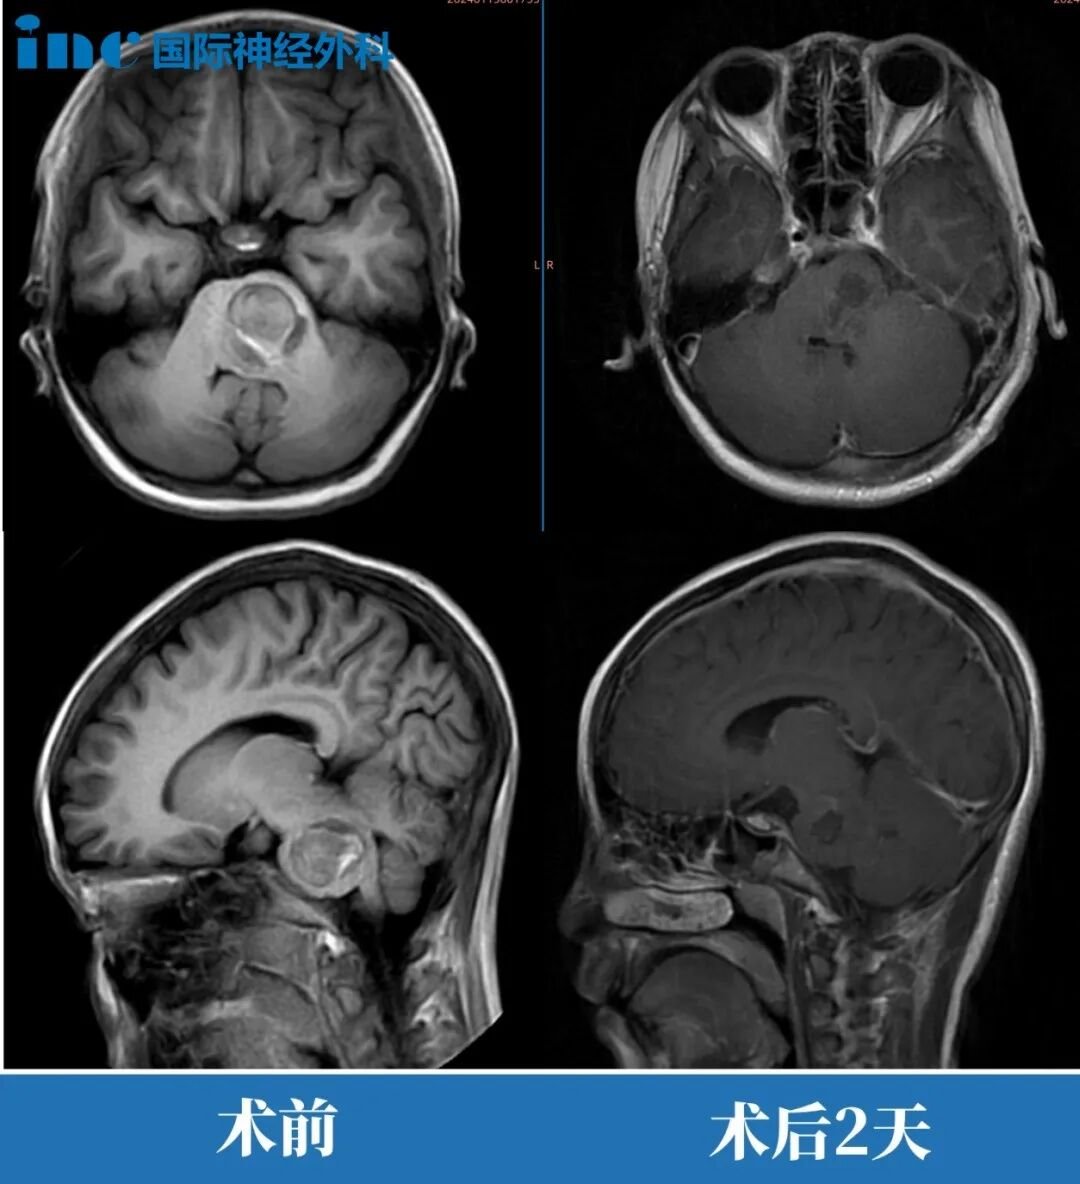

次日清晨,小晴接受手术治疗。在巴特朗菲教授主刀下,手术顺利完成,海绵状血管瘤实现完全切除。术后当晚,吴先生通过监护系统观察到女儿已恢复语言功能,这一超出预期的恢复效果令全家倍感欣慰。

原定需要监护观察2天的小晴,提前1天转入普通病房。此时患儿肢体活动功能恢复正常,可自主进食,精神状态良好。术后2个月随访时,小晴已完全回归校园生活。巴特朗菲教授在复查影像学资料后表示:"影像学表现优异,脑干形态已恢复正常。"